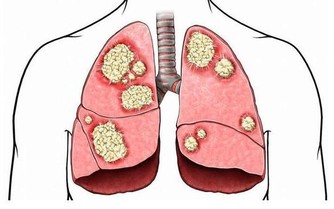

骨質疏鬆即骨質疏鬆症,是多種原因引起的一組骨病,骨組織有正常的鈣化,鈣鹽與基質呈正常比例,以單位體積內骨組織量減少為特點的代謝性骨病變。在日常的生活中,我們最常見的骨質疏鬆的症狀就是骨頭疼痛,身長縮短、駝背,容易骨折,還有就是呼吸功能下降。